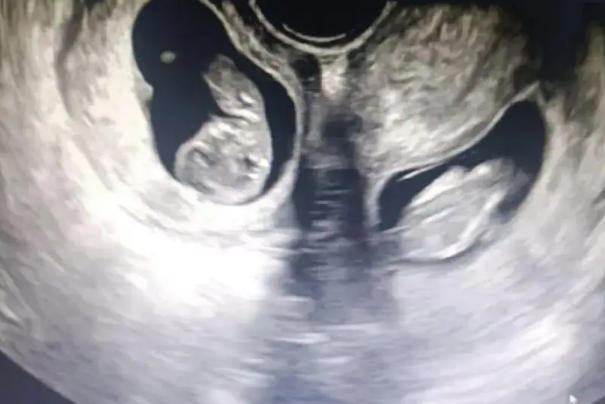

怀孕6-8周首次B超确认双胎妊娠,费用与单胎相近,约150-250元。这个阶段主要确认孕囊数量、胎心搏动,判断是单卵双胎还是双卵双胎。